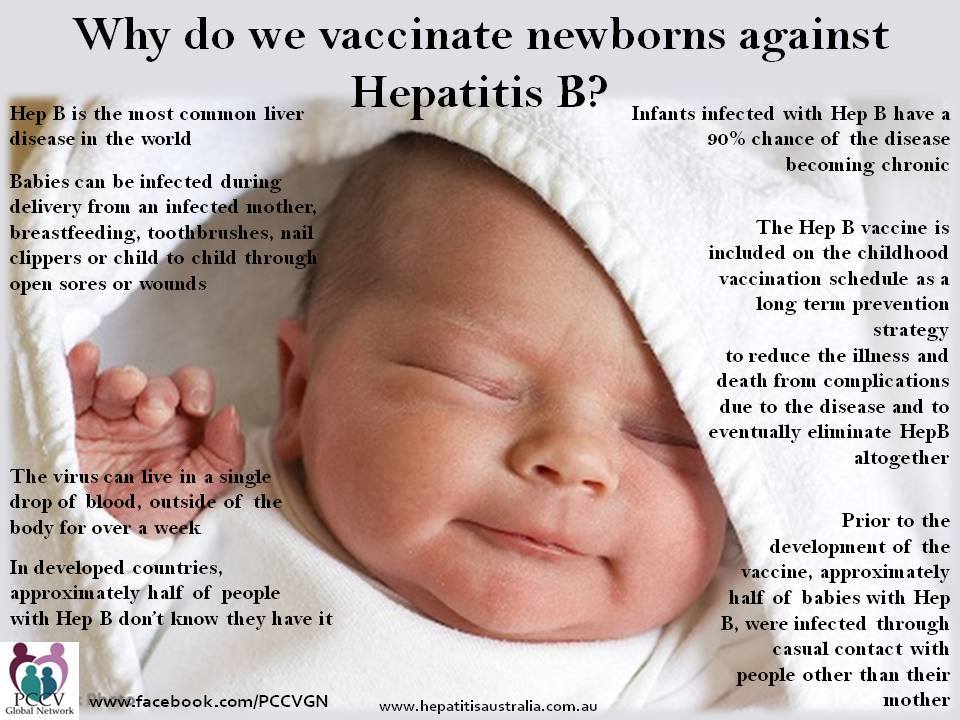

Hepatitis B

Virus, infected blood (survives outside body for 7 days)

Virus, infected blood (survives outside body for 7 days)- Symptoms: fever, fatigue, loss of appetite, nausea, vomiting, jaundice (yellowing skin)

- Complications: scarring of the liver, cirrhosis, cancer

- Deaths/Statistics: in 2007, 43,000 new infections in the US,

- 800,000 to 1.4 million have chronic hepatitis B virus infection, 30-40% of these infections were acquired during childhood

- Globally, chronic Hep B affects 350 million people, contributes to an estimated 620,000 deaths worldwide each year.

- Hepatitis B is a contagious liver disease that ranges in severity from a mild illness lasting a few weeks to a serious, lifelong illness. It results from infection with the Hepatitis B virus. Hepatitis B can be either “acute” or “chronic.”

- Acute Hepatitis B virus infection is a short-term illness that occurs within the first 6 months after someone is exposed to the Hepatitis B virus. Chronic Hepatitis B virus infection is a long-term illness that occurs when the Hepatitis B virus remains in a person’s body.

- It is true that hepatitis can be acquired from sexual intercourse and shared needles. So why immunize infants and children? Because infection can occur from any blood contact, whether at birth or other exposures.

- 90% of infants who are infected will ultimately develop chronic hepatitis. Only 30% of children age 1-5 develop chronic hepatitis, and only 5-10% of healthy adults who are infected will develop chronic infection.